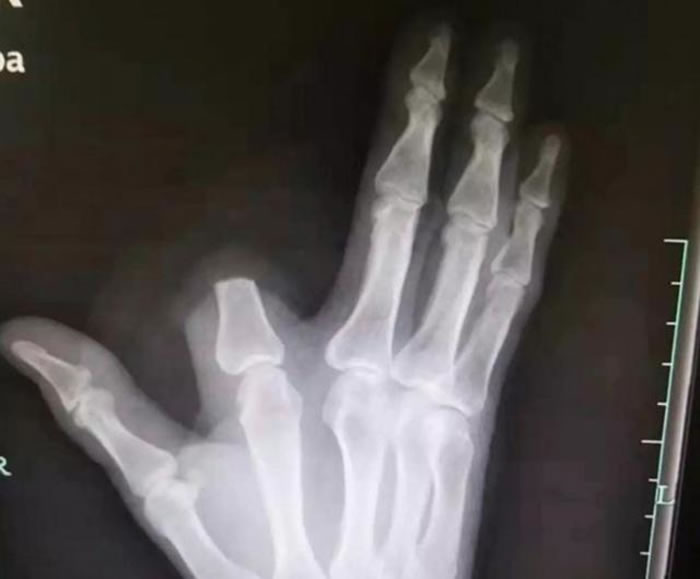

(神秘的地球uux.cn报道)据《南华早报》报道称,中国一位农民在被毒蛇咬伤后切掉了自己的手指。此后他去医院就医,那里的医生对他解释说,他的预防措施有点过了,没必要这样。

农民在浙江绍兴市上虞区砍柴,当时毒蛇咬伤了他的食指。稍加思索后他砍掉了自己的手指。他认为,毒蛇会让他丧命于此。但是医生解释说这条蛇毒性没有那么大,最主要的是要及时就医并且服用解毒药。